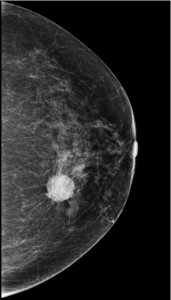

Caso 22

Explicación: Al tener 85 años, la mama tendrá un patrón graso y la lesión se verá fácilmente. Se hacen ambas proyecciones para tener una visión completa de la mama.